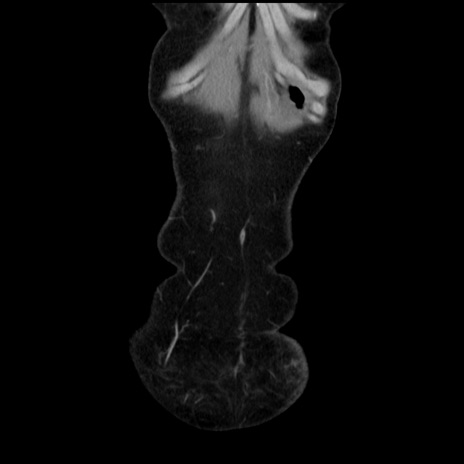

矢状断像